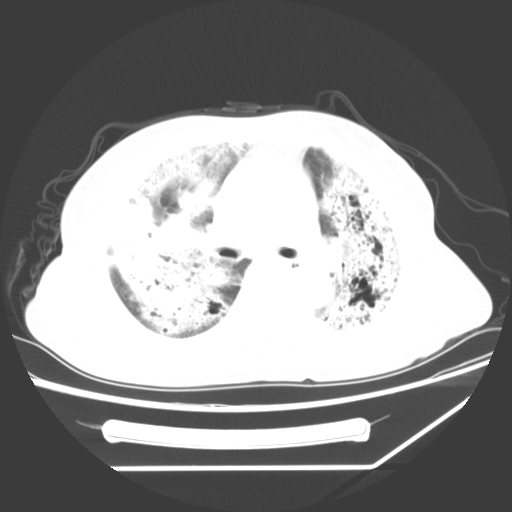

1、左肺中央型肺癌并双肺弥漫性转移   2、双肺部感染    3、肺大泡     4、左侧胸腔积液

双侧肺弥漫性病变,可见“空泡征”及“蜂窝征”,考虑肺泡癌可能性大,左侧胸腔积液,考虑胸膜受累可能!

考虑肺泡癌,建议排除感染。

考虑肺泡癌

1)不排除肺泡癌可能。2)左侧胸腔积液。